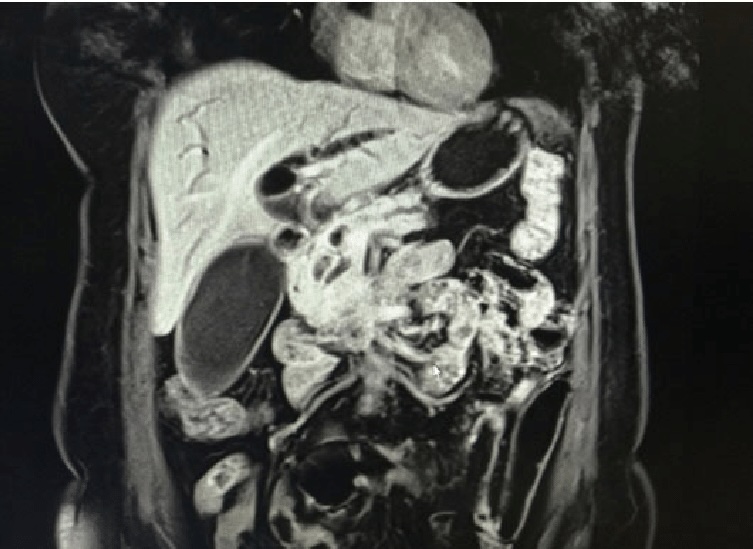

Магнитно-резонансная томография при подозрении на водянку желчного пузыря проводится в режиме аксиальной и коронарной Т2-взвешенной томографии с жироподавлением, с последующим выполнением нативной магнитно-резонансной холангиографии. Исследование направлено на визуализацию увеличенного желчного пузыря, признаки его обтурации и состояния желчевыводящих путей. Признаки являются прямыми и анатомическими.

МРТ выявляет следующие анатомические признаки водянки желчного пузыря:

На Т2-взвешенных изображениях определяется гиперинтенсивный сигнал от избыточно расширенной полости желчного пузыря с продольным размером более 10 см и поперечным более 4 см.

Стенка желчного пузыря равномерно истончена, толщина не превышает 3 мм, контуры гладкие, без признаков воспалительной инфильтрации.

В шейке желчного пузыря или пузырном протоке может определяться структура с низким сигналом, соответствующая обтурирующему конкременту.

Жёлчные протоки дистальнее уровня блока не визуализируются или представлены утончённой линией без сигнала, что указывает на механическую обструкцию.

Общий жёлчный проток может быть нормального диаметра или умеренно расширен, в зависимости от длительности блока.

Окружающие структуры не изменены, признаков отёка, инфильтрации или воспалительного процесса не определяется.